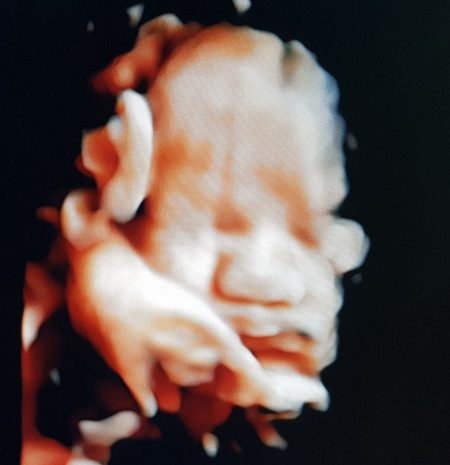

ความสุขของแม่

เอารูปมาอวดค่ะเห็นแค่นี้ก็มีความสุขแล้ว

ลูกน้อย